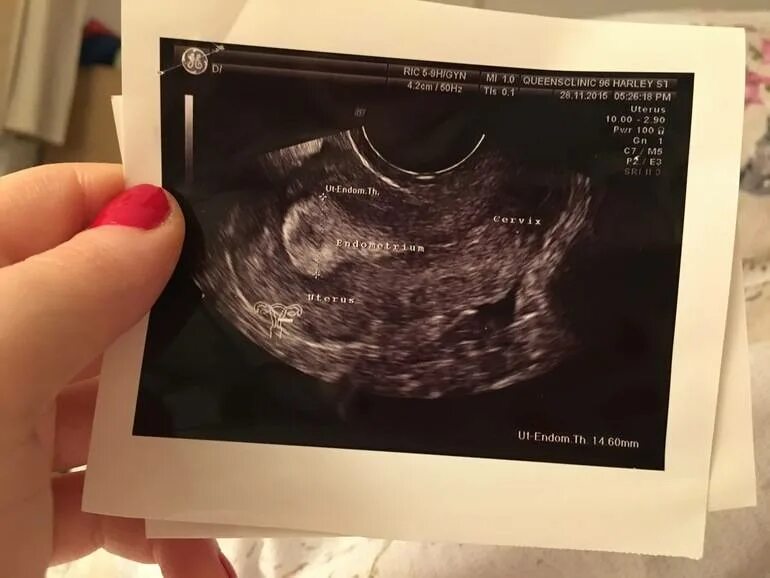

Тест показал а узи нет